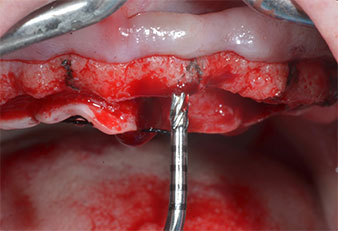

Пиезоелектрически инструмент с диамантено покритие с форма на пламък (Piezomed I1) e използван за маркиране на позициите на имплантите и за пилотна подготовка (Фиг. 3). Препарацията беше извършена с внимателни вертикални движения, с намалена мощност, пълна иригация и лек натиск (под 300 g) След това се приложи пилотен инструмент (Piezomed I2A/ I2P) за първоначално увеличение на диаметъра на имплантното ложе с 2 mm (Фиг. 4), последвано от 3 mm разширение (Фиг. 5)

В случай на твърда кост, цялата поредица от инструменти, включително междинните инструменти Piezomed Z25P и Z35P, трябва да се използват за разширяване на остеотомиите.

В настоящия случай инструменти Z25P и Z35P не са използвани поради сравнително меката задна кост, която лесно се обработва с I3A/I3P.

Поради сравнително твърдата кост (D2) в тази област, 10-милиметровото имплантно ложе в позиции 11 и 21 беше завършено с ротационен дрил с диаметър 4 mm в комбинация с W&H хирургичен обратен наконечник WS-75 L, W&H имплантологичен мотор Implantmed и опционалния W&H Osstell ISQ модул. За разлика от това, благодарение на меката кост, дисталните зони се подготвят до окончателен диаметър 3 mm, използвайки накрайник за Piezomed I3P. Имплантите най-накрая са поставени трансгингивално, за да остеоинтегрират за три месеца (Фиг. 6-10). Съществуващата протеза се фиксира на четирите временни импланта (Фиг. 8).